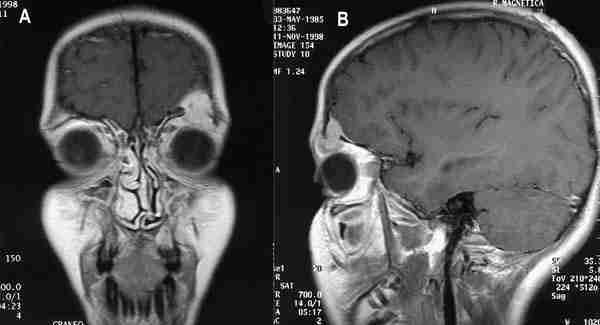

En este sentido, la realización de secuencias de RM potenciadas en T1 con gadolinio y matrices de alta resolución resulta muy útil, en nuestra experiencia, para evaluar el resto activo de los retinoblastomas, diferenciándolo del componente cálcico y medir exactamente su localización y tamaño (figura 14).

53-14.jpg (14744 bytes)

Figuras 14a y b. Resto tumoral activo de retinoblastoma que se diferencia en secuencia T1 con gadolínio del componente óseo, para realizar mediciones previa a la colocación de la placa radioactiva.

Control del intervalo quirúrgico en los casos de tratamientos quirúrgicos en varios tiempos: implantes porosos. Las técnicas de imagen pueden ser muy útiles a la hora de decidir el momento de las distintas fases en tratamientos con varias cirugías. Es el caso de la colocación de prótesis oculares porosas de hidroxiapatita (HA) o MEDPOR, La RM permite un control de la revascularización que se produce en la prótesis y que es necesaria para una correcta implantación del vástago en el que se anclará la prótesis externa.

La sección de Oftalmología infantil y la sección de Neurorradiología del Hospital Universitario La Paz, hemos realizado un estudio prospectivo mediante RM para valorar la existencia o no de revascularización en función del grado de captación de Gd en 39 niños (20 niñas y 19 niños) sometidos a enucleación o evisceración uni o bilateralmente y de edades comprendidas entre los 3 meses y los 2 años por diferentes patolo gías de base, colocando en 10 casos prótesis de MEDPOR y en 29 niños prótesis de hidroxiapatita (en un caso de forma bilateral). Se realizaron secuencias potenciadas en T1, con saturación grasa y reconstrucciones axiales y sagitales de 3 mm con matriz de alta resolución antes y después de la administración de gadolinio. La RM nos permitió evaluar diferentes parámetros como el grado de captación (sinónimo de revascularización del implante), la forma de captación (homogénea o heterogénea), el lugar de comienzo (anterior o posterior), la existencia o no de captación extraprótesis como índice de infección periprótesis y la presencia o no de líneas que sugieran fisuras o alteraciones intrínsecas de la prótesis. Estos parámetros fueron comparados con la evolución y el estado de la prótesis en el acto quirúrgico de la colocación del vástago, evaluando el grado de correlación entre los hallazgos en la RM y los datos clínicos y quirúrgicos (figura 15).

53-15.jpg (13343 bytes)

Figuras 15a, b, c y d. Secuencias T1 con gadolínio intravenoso y saturación grasa de prótesis porosas. Captación completa de la prótesis en (a). Falta la vascularización anterior en la prótesis (b, c). Línea de fractura de la prótesis (d).

Los resultados de nuestro estudio muestran una forma de vascularización bastante constante, empezando por el polo posterior, con un patrón homogéneo, y quedando la parte anterior como última zona para vascularizar. Esto podría explicar la aparición de exposiciones anteriores y malas implantaciones de vástagos en los casos de prótesis sin buena vascularización anterior. Por ello, es especialmente importante que sea prácticamente completa antes de la colocación del vástago, o, por lo menos, la de la región anterior. Respecto al tiempo de esta revascularización, nuestros resultados coinciden con los referidos en la literatura, siendo necesario casi un año en el caso de las prótesis HA para lograr un 75-80 por ciento y un tiempo algo menor para las prótesis MEDPOR. Son llamativas las diferencias en la sensibilidad de la RM para las prótesis de MEDPOR y las de HA, significativamente menor en la primera. Hay que tener en cuenta, sin embargo, varios hechos a la hora de evaluar estos resultados como el escaso número de prótesis de MEDPOR estudiadas con RM por el momento (solo diez) y el hecho de que en todos los casos en los que ha existido una mala correlación clínico-radiológica el recubrimiento era de esclera. Quizá este tipo de recubrimiento dificulta la valoración de la captación. También puede ser que el MEDPOR pueda dar lugar a más variabilidad en la forma de captación. De hecho, el patrón y la forma de evolución de la captación son menos constantes en el MEDPOR que en la HA.

En conclusión, y de acuerdo con otros trabajos, la RM es un método útil y de alta fiabilidad en el control de las prótesis sobre todo de HA. Asimismo, la RM es especialmente útil para la detección de complicaciones en ambos tipos de prótesis (36-39).